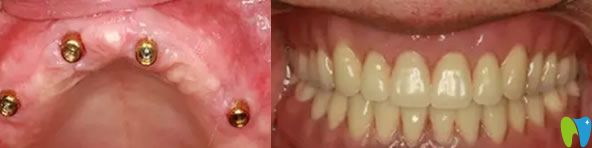

雅悅齒科全口無牙種植牙前后效果對比圖

老媽的牙齒,可能因為生活習(xí)慣的原因,導(dǎo)致牙齒脫落嚴(yán)重,按了活動假牙,當(dāng)時對于口腔牙齒也不是很了解,覺著活動假牙價格合適。按上之后,感覺強度不是太好,吃東西容易塞牙,造成目前,牙齦有點萎縮。來院經(jīng)過王杰院長檢查后,需要對牙齦萎縮進行治療,炎癥得到控制后在再進行種植牙修復(fù)。

全口數(shù)字化X光影像

經(jīng)過一個月的漫長等待,老媽終于做了種植牙,當(dāng)場就拿蘋果做實驗,感覺種出來的牙齒和真牙一樣舒服。老媽再次擁有滿口舒適的好牙,恢復(fù)了咀嚼功能,真心覺得很不錯,感覺醫(yī)生技術(shù)水平也很專業(yè),很細心,走的時候還給我們囑咐種植牙的術(shù)后護理方法。

老媽種植牙的術(shù)后效果真實照片